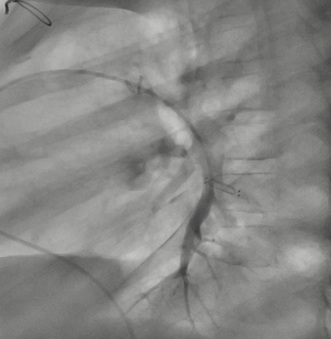

Catheterization was naturally indicated for managing his condition. We first performed an ultrasonic evaluation of his femoral veins to ensure they had at least a 3 mm axial diameter. After securing vascular access, angiographic verification of the right femoral vein patency and diameter was performed. We conducted a standard diagnostic hemodynamic catheterization under fluoroscopic control in a biplane system (Artis Zee, Siemens®) with a low dose protocol. Then, pump injection with diluted contrast (0.5 ml of isosmolar contrast per kg of body weight, diluted with isotonic saline solution in a 70% contrast to 30% saline ratio) into the left pulmonary artery was achieved with biplanar acquisition at 15 images per second (Figures 1 & 2). This process was to examine the left lung pulmonary arterial architecture to find an ideal implantation site, requiring a length of at least 30 mm with initial and final diameters of 7 and 5 mm, respectively, and a bifurcation pattern showing branches larger than 3 mm in diameter. Once the target site was selected, the angiographic catheter was exchanged over a conventional 0.035 guidewire, which served as a support for successive dilations of the venous access point until the 12 F introducer advanced without resistance. A multipurpose 5F catheter was then advanced over the guidewire, followed by a 0.35 hydrophilic guidewire to position the catheter in the selected segment. After removing the hydrophilic guidewire, a small manual contrast injection was performed to evaluate the distal anatomy before advancing a 0.018” guidewire through the catheter, ensuring the floppy segment did not distort or angle and that a non-floppy portion was present at the device implantation site. With these considerations meticulously observed, and the catheter removed, the catheter housing the CardioMEMS was advanced, ensuring smooth and natural progression until reaching the destination and proceeding with its release. Following this, the catheter was removed, and the previous multipurpose catheter was reinserted to a position proximal to the device's release point. A manual contrast injection was then performed through the catheter via a Y-connector without removing the guidewire, and biplanar images were acquired to assess the occupied volume of the device, its loops, and any potential interference with the distal filling of that branch or collateral vessels. High-quality pulmonary pressures were obtained through CardioMEMS®, so the procedure was concluded without any problems related to the device or vascular access. Successful monitoring of the pulmonary pressures facilitated the management of this challenging patient, and a heart transplant was successfully performed 13 months later. The surgery required extensive manipulation of the patient's thorax, which, as evidenced in radiographs taken in the following days, led to displacement of the device that did not interfere with measurements. The patient underwent subsequent catheterizations for post-transplant protocolized control without complications in vascular access, performed through the same right femoral vein. On two occasions, an excellent correlation was observed between the invasive measurements of pulmonary pressures and the results from the CardioMEMS check. During a recent catheterization, within the regular control indications with the patient weighing 28 kg, this correlation was confirmed, and an angiography was performed on the left pulmonary branch showing the arterial vascular architecture (Figures 3 & 4). Despite the displaced device, there is no interference or obstruction to the permeability of the lobar and sub segmental branches in angiography nor in pressures distal or proximal and an excellent correlation was obtained between invasive (Figure 5) and CardioMEMS® measurements (Figure 6). The procedure confirmed the permeability of the pulmonary branches, reaffirming the utility of the device for continuous and non-invasive monitoring in a pediatric context.

Figure 2: Lateral angiography of left inferior lobar pulmonary artery pre-CardioMEMS® Implantation.